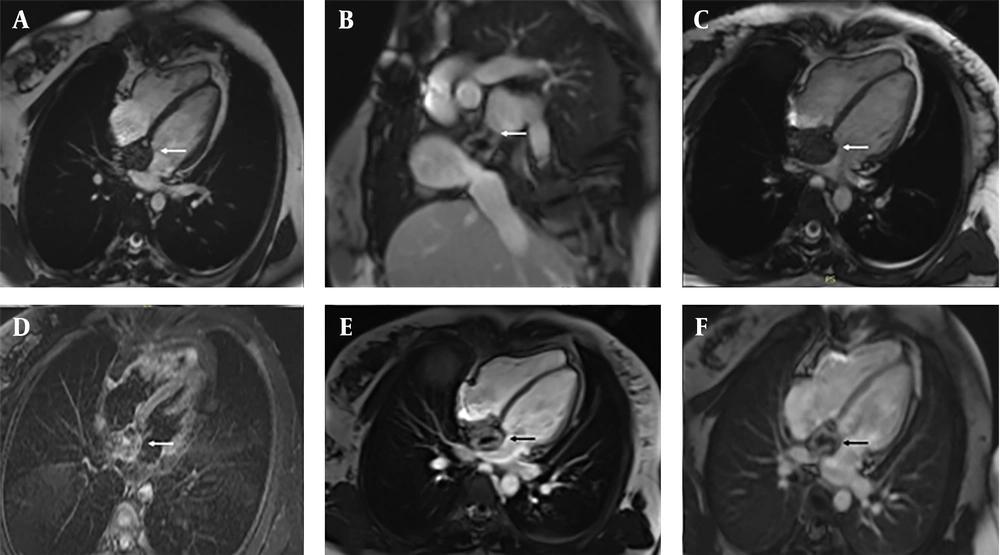

Initial transthoracic echocardiography (TTE) showed a 4.2 × 3.8 cm hyperechoic mass involving the IAS, extending into the RA and causing partial obstruction of the SVC. Cardiac magnetic resonance imaging (MRI) in March 2023 revealed a heterogeneous mass (4.2 × 3.8 × 3.5 cm; Figure 1). Steady-state free precession (SSFP) cine sequences in the axial plane showed an iso-intense mass localized to the IAS with extension into the RA. The sagittal view demonstrated tumor encroachment into the SVC, causing partial obstruction. T2-weighted axial images displayed a heterogeneous hyperintense signal, suggestive of edema or inflammation, while Short Tau inversion recovery (STIR) axial sequences showed a non-homogeneous iso-intense signal with areas of hyperintensity. On T1-weighted axial images, the mass presented with a non-homogeneous iso-intense signal and hypointense foci. Dynamic perfusion imaging revealed avid enhancement, indicating significant vascularity. Post-contrast imaging showed significant enhancement on early gadolinium enhancement (EGE) sequences with foci of non-enhancement, suggestive of thrombus or necrosis. Late gadolinium enhancement (LGE) sequences confirmed heterogeneous enhancement with central non-enhancing areas, consistent with necrosis or fibrosis.

Cardiac magnetic resonance (CMR) imaging of a patient with postoperative inflammatory pseudotumor (IPT) following atrial septal defect (ASD) repair. A large heterogeneous right atrial mass is demonstrated: A, axial SSFP cine view showing a large mass occupying most of the right atrial cavity; B, sagittal view demonstrating the extent of the lesion and its relationship to adjacent mediastinal structures; C, four-chamber SSFP cine view revealing the mass protruding into the right atrial lumen and partially obstructing blood flow; D, axial STIR image showing a heterogeneous isointense-to-hyperintense signal with focal areas of high intensity; E, early gadolinium enhancement (EGE) image demonstrating strong peripheral enhancement with multiple non-enhancing foci, suggestive of thrombus or necrosis; F, late gadolinium enhancement (LGE) image confirming persistent peripheral enhancement with central non-enhancing areas, consistent with necrosis or organized thrombus.